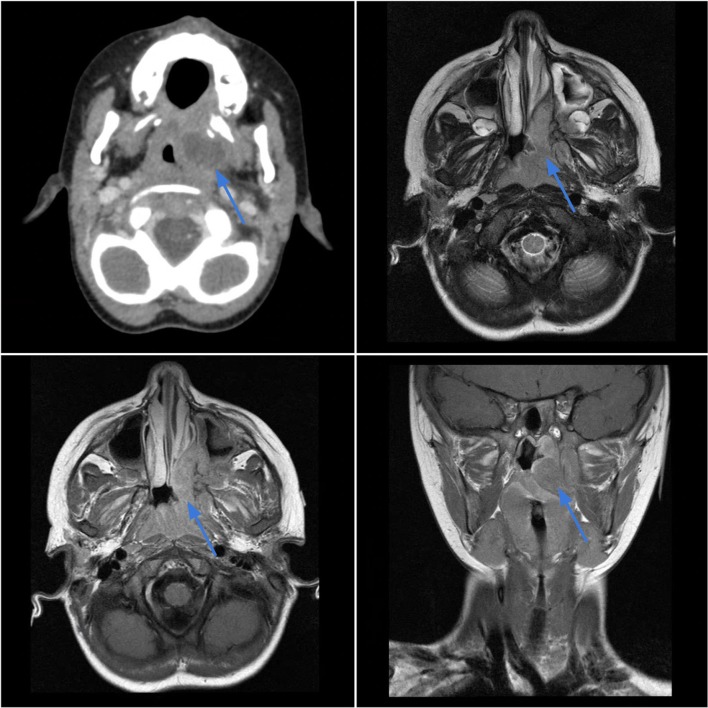

Case 3.

Ewing sarcoma of the left nasopharynx in a 3-year-old female with left ear pain and a visible oropharyngeal mass. Axial contrast-enhanced CT (top left) shows an infiltrative soft tissue mass in the left nasopharynx which displaces the nasal septum and invades the nasal cavity floor and roof of the soft palate. The lesion demonstrates intermediate T2 signal intensity (top right) with heterogeneous contrast enhancement on T1-weighted sequences (bottom images)